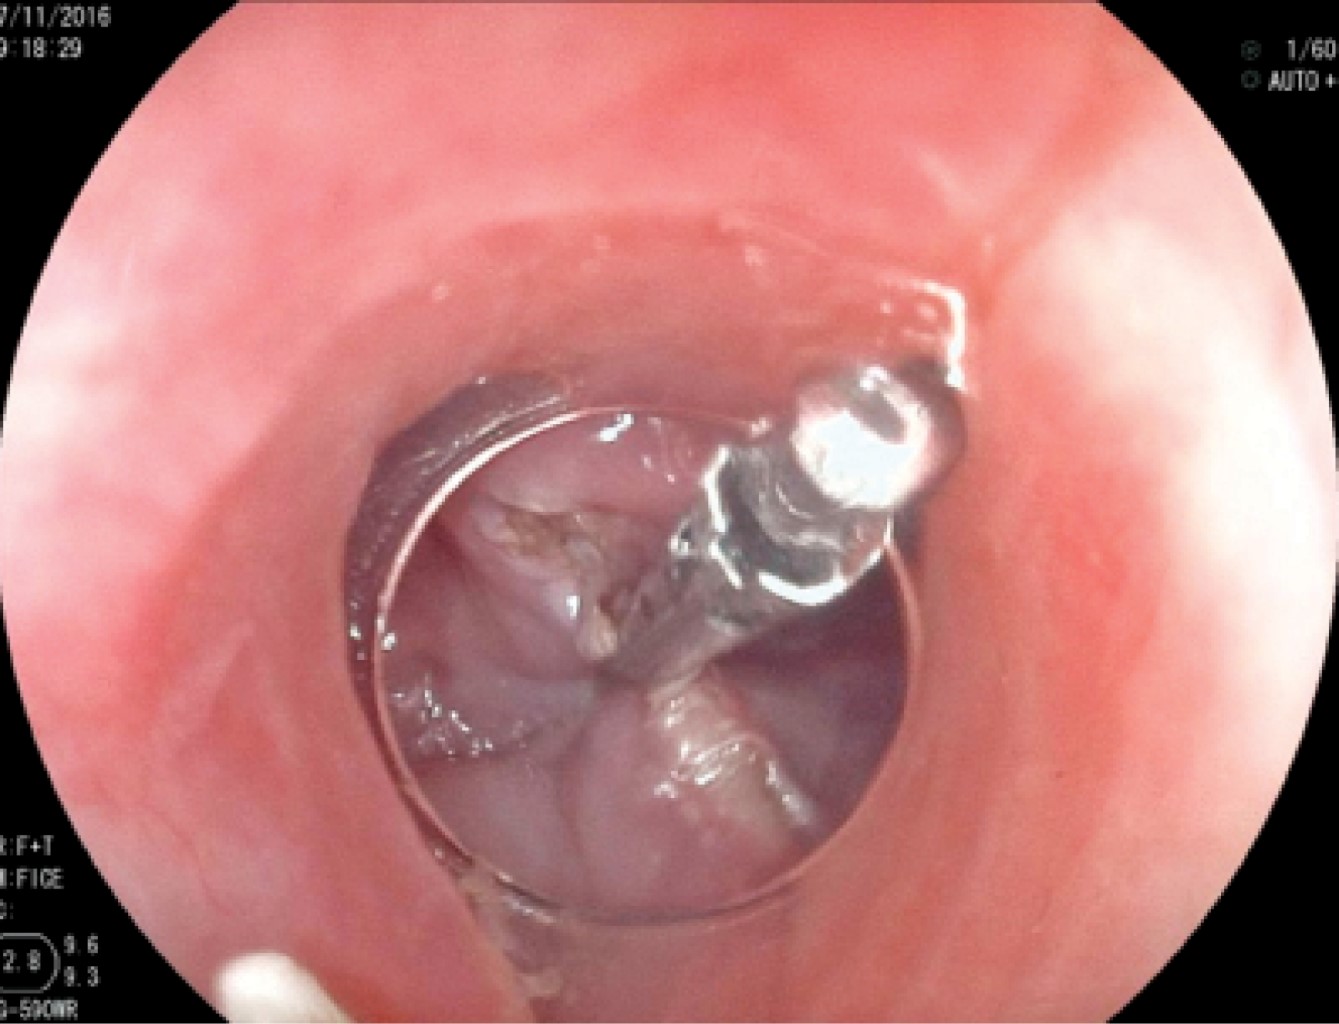

En los primeros 10 pacientes una vez identificada la luz del esófago, se introdujo una guía metálica a la cavidad gástrica y sobre ésta un dilatador de Savary Gilliard de 7 mm o 21 Fr, el cual llega hasta el estómago y se deja en ese sitio. Lo anterior delimita adecuadamente la luz del divertículo y del esófago (Figura 2). En el extremo distal del tubo de inserción del endoscopio se coloca un capuchón plástico transparente (MBL 6-1 Cook Endoscopy) que se utiliza como espaciador, lo que permite identificar el septum del músculo cricofaríngeo. En los primeros 10 casos se utilizó un videogastroscopio Olympus modelo GIF-H140 y procesador de imagen CV-140 Olympus (Olympus Optical Co., Tokio, Japón) de 9.8 mm de diámetro, la unidad electroquirúrgica Olympus UES-40 SurgMaster, y como disector un cuchillo aguja (Needle Knife, Cook Endoscopy, Winston-Salem, NC), se hace un corte en el borde de la luz esofágica en la parte media del septum y hacia la luz del divertículo. Se realiza primero el corte de la mucosa exponiendo las fibras musculares del cricofaríngeo (Figura 3), el corte se profundiza hasta completar la sección de las fibras transversales del esfínter cricofaríngeo, sin necesariamente llegar al fondo del divertículo (Figura 4), lo que permite la aproximación de los bordes de la incisión en la mucosa con clips metálicos evitando la perforación y riesgo de sangrado (Figura 5). A los cuatro pacientes restantes se les aplicó la técnica de POEM (miotomía endoscópica peroral), infiltrando la submucosa con solución fisiológica y azul de metileno para levantar la mucosa, posteriormente, se corta la mucosa con el hidrodisector HybridKnife, tipo T-type marca ERBE que es un instrumento multifuncional que combina tecnología electroquirúrgica e hidrodisección en un solo instrumento con el cual se realiza un levantamiento de la mucosa y la creación de un túnel submucoso, seccionando sólo las fibras musculares transversales y finalmente cerrando la entrada del túnel con clips endoscópicos. En estos pacientes se utilizó un videogastroscopio Fujinon, procesador de imágenes Fujifilm Processor VP-4450HD, unidad electroquirúrgica ERBE VIO 200 D y el HybridKnife de ERBE, T-type (marcas registradas) utilizando corriente de corte y coagulación pura (50 W). Por último se retira el dilatador de Savary Gilliard y posterior al procedimiento se efectuó un trago de material hidrosoluble para descartar fugas. A todos los pacientes se les administró una dosis única de antibiótico al inicio del procedimiento y fueron manejados de forma ambulatoria en domicilio iniciando con dieta líquida a las cuatro horas.

Figura 5